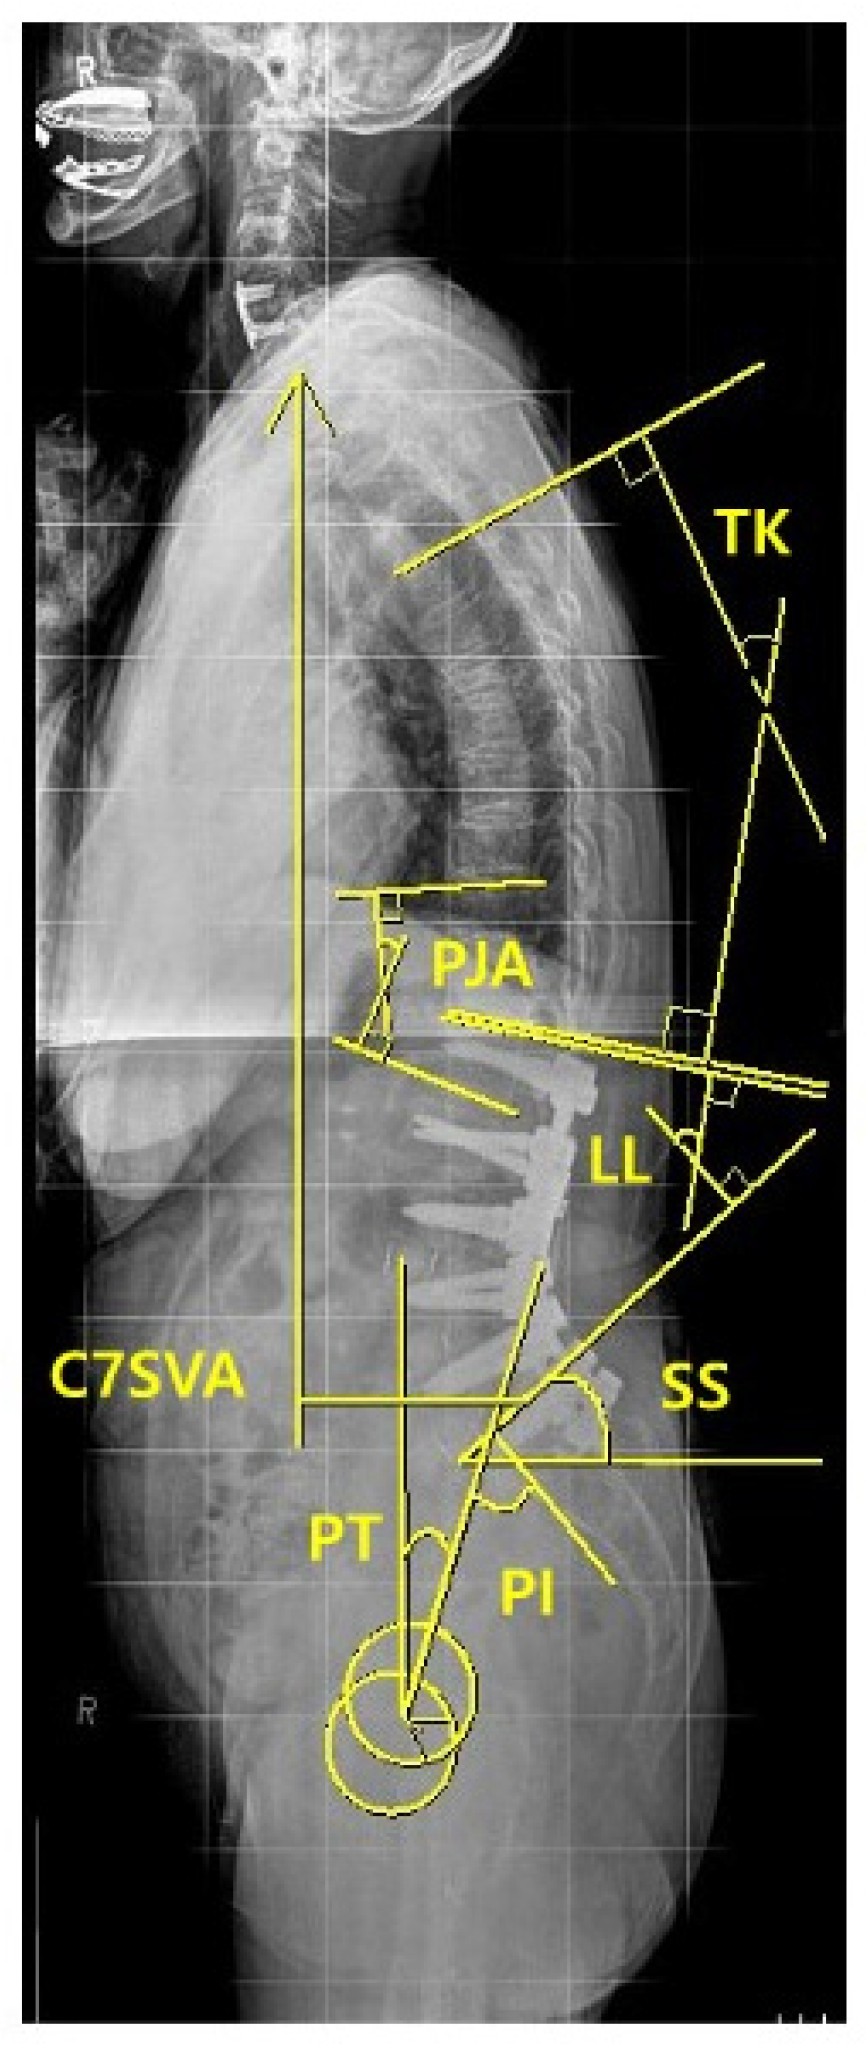

For the radiographic assessment of spinopelvic parameters, standing 36-inch-long cassette AP and lateral radiographs of the whole spine were measured at the preoperative, immediate postoperative, and regular postoperative outpatient visits (3, 6, 9 months, and 1-year, 2-year, and the final follow-up), respectively. On the radiographs, C7 sagittal vertical axis (C7SVA), thoracic kyphosis (TK) [18], thoracolumbar kyphosis (TLK) [18,19], lumbar lordosis (LL) [18], sacral slope (SS) [18], pelvic tilt (PT) [18], pelvic incidence (PI) [18,19,20], and proximal junctional angle (PJA) were measured (Figure 3). We also collected and analyzed the change (preoperative minus postoperative) of each radiographic parameter between the preoperative and the immediate (3 months) postoperative.

Figure 3.

Measurement of sagittal spinopelvic parameters.